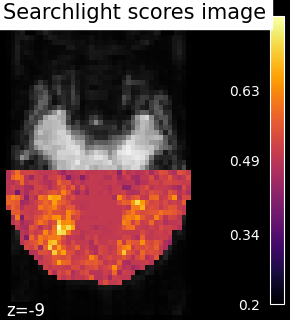

5.5.4.1. Searchlight¶

The results of the searchlight can be found in the scores_ attribute of the

SearchLight object after fitting it to the data. Below is a

visualization of the results from Searchlight analysis of face

vs house recognition.

The searchlight was restricted to a slice in the back of the brain. Within

this slice, we can see that a cluster of voxels in visual cortex

contains information to distinguish pictures showed to the volunteers,

which was the expected result.